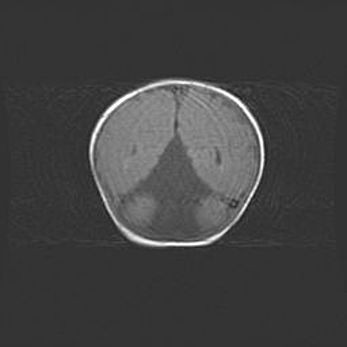

Сообщающаяся гидроцефалия. Кистозная энцефаломаляция головного мозга.

Возраст: 3 месяца 4 дня

Вес: 3100 г

Пол: женский

Окружность головы: 34 см

Срок гестации: 31 неделя

Кистозная энцефаломаляция головного мозга - одна из форм поражения головного мозга в детском возрасте. Характеризуется возникновением множественных и распространённых кист в коре, белом веществе и подкорковых образованиях головного мозга у плодов, новорождённых и детей раннего возраста. Развитие кистозной энцефаломаляции связано с внутриутробной асфиксией и гипотонией, родовой травмой, тромбозом синусов, пороками развития сосудов, инфекциями, сепсисом и другими причинами. Наиболее значимые инфекционные агенты: вирусы простого герпеса, цитомегалии, краснухи, токсоплазмы, энтеробактерии, золотистый стафилококк и другие.